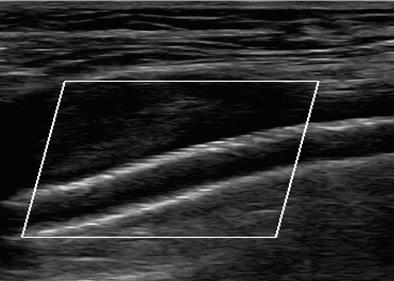

58 УСТРОЙСТВА ЗА ЗАТВАРЯНЕ НА ПУНКЦИОННИ МЕСТА (VASCULAR CLOSURE DEVICES) – КЛИНИЧНО ПРИЛОЖЕНИЕ Р. Рунков

60 КЪСНА РЕВАСКУЛАРИЗАЦИЯ СЛЕД ОСТРА ТРОМБОЗА НА А. СУБКЛАВИА СИНИСТРА –КЛИНИЧЕН СЛУЧАЙ Р. Рунков

62 РЕТРОГРАДНА ПЕРКУТАННА

Лактазна неустойчивост. Състоянието (хиполактазия) е най-често срещаната физиоло -

гична причина за LI. Макар